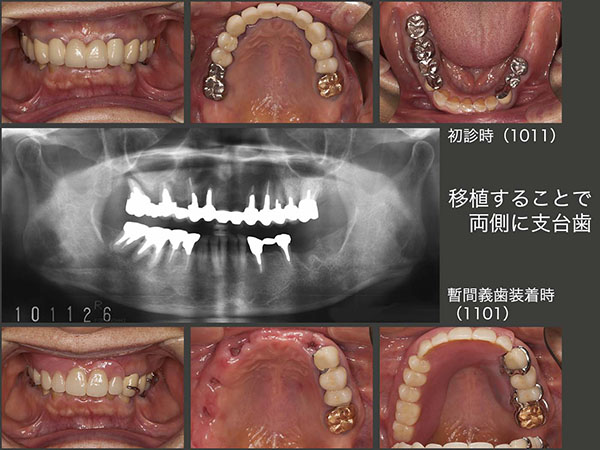

7.移植することで両側に支台歯

2010年11月初診,66歳女性.上顎は,歯根破折,歯根穿孔,歯肉縁下カリエスが深いが原因で合計5本抜歯することになった.特に右上の犬歯を失うことは,義歯の安定にとって影響が大きい.左側のみの片側支台歯となるので,右側では咬みにくくなること,初めての義歯なので義歯床の異物感および発音障害が生じるであろう等,詳しく,しつこいぐらいに説明しておいた.その後11年1月の正月明けに,抜歯と同時に義歯を装着した.実際に装着して,患者さんの反応は予想どおりに最悪であった.残っている歯の数でなく,歯の配置(両側にあること)が義歯の安定にとって重要である.

義歯を安定させるためには,右側にも支台歯が必要である.言い換えれば,左側に4本あっても偏在では義歯が安定しにくい.そこで左上5を右側に移植する治療計画をたてた.まずドナー歯を抜きやすくするために,矯正的挺出を行った.右側は,インプラテックス社製 T’sボーンスプレッディングを用いて顎堤の幅を拡大したのち,ドナー歯を90°回転して植立した(2011年11月).さらに,矯正用ミニインプラントを植立し,移植歯の固定を強固にした.

初診時と初診終了時のデンタルX線写真の比較.左下のスライドは2020年1月の状態.19年12月に左下のコーヌス義歯を紛失し,今度は固定式を強く希望したため,内冠はそのままにしてブリッジを装着した.この患者さんは咬合力が強く,とにかく強く咬まないように気を遣ってくださいとお願いしている.右上移植歯は健在である.